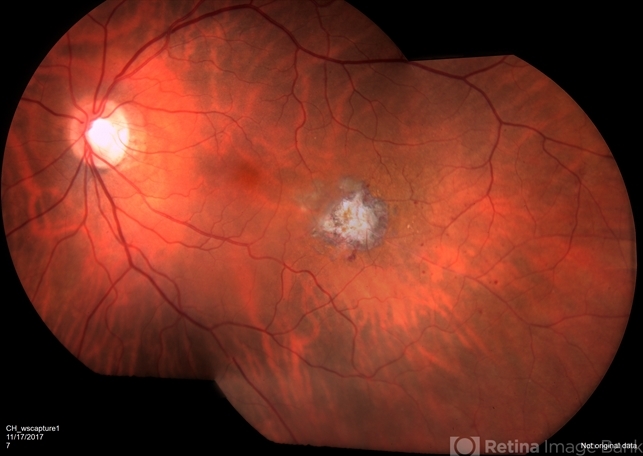

- retinal macroaneurysm, focal laser

- Fundus camera

- Repaired retinal macroaneurysm with focal laser.